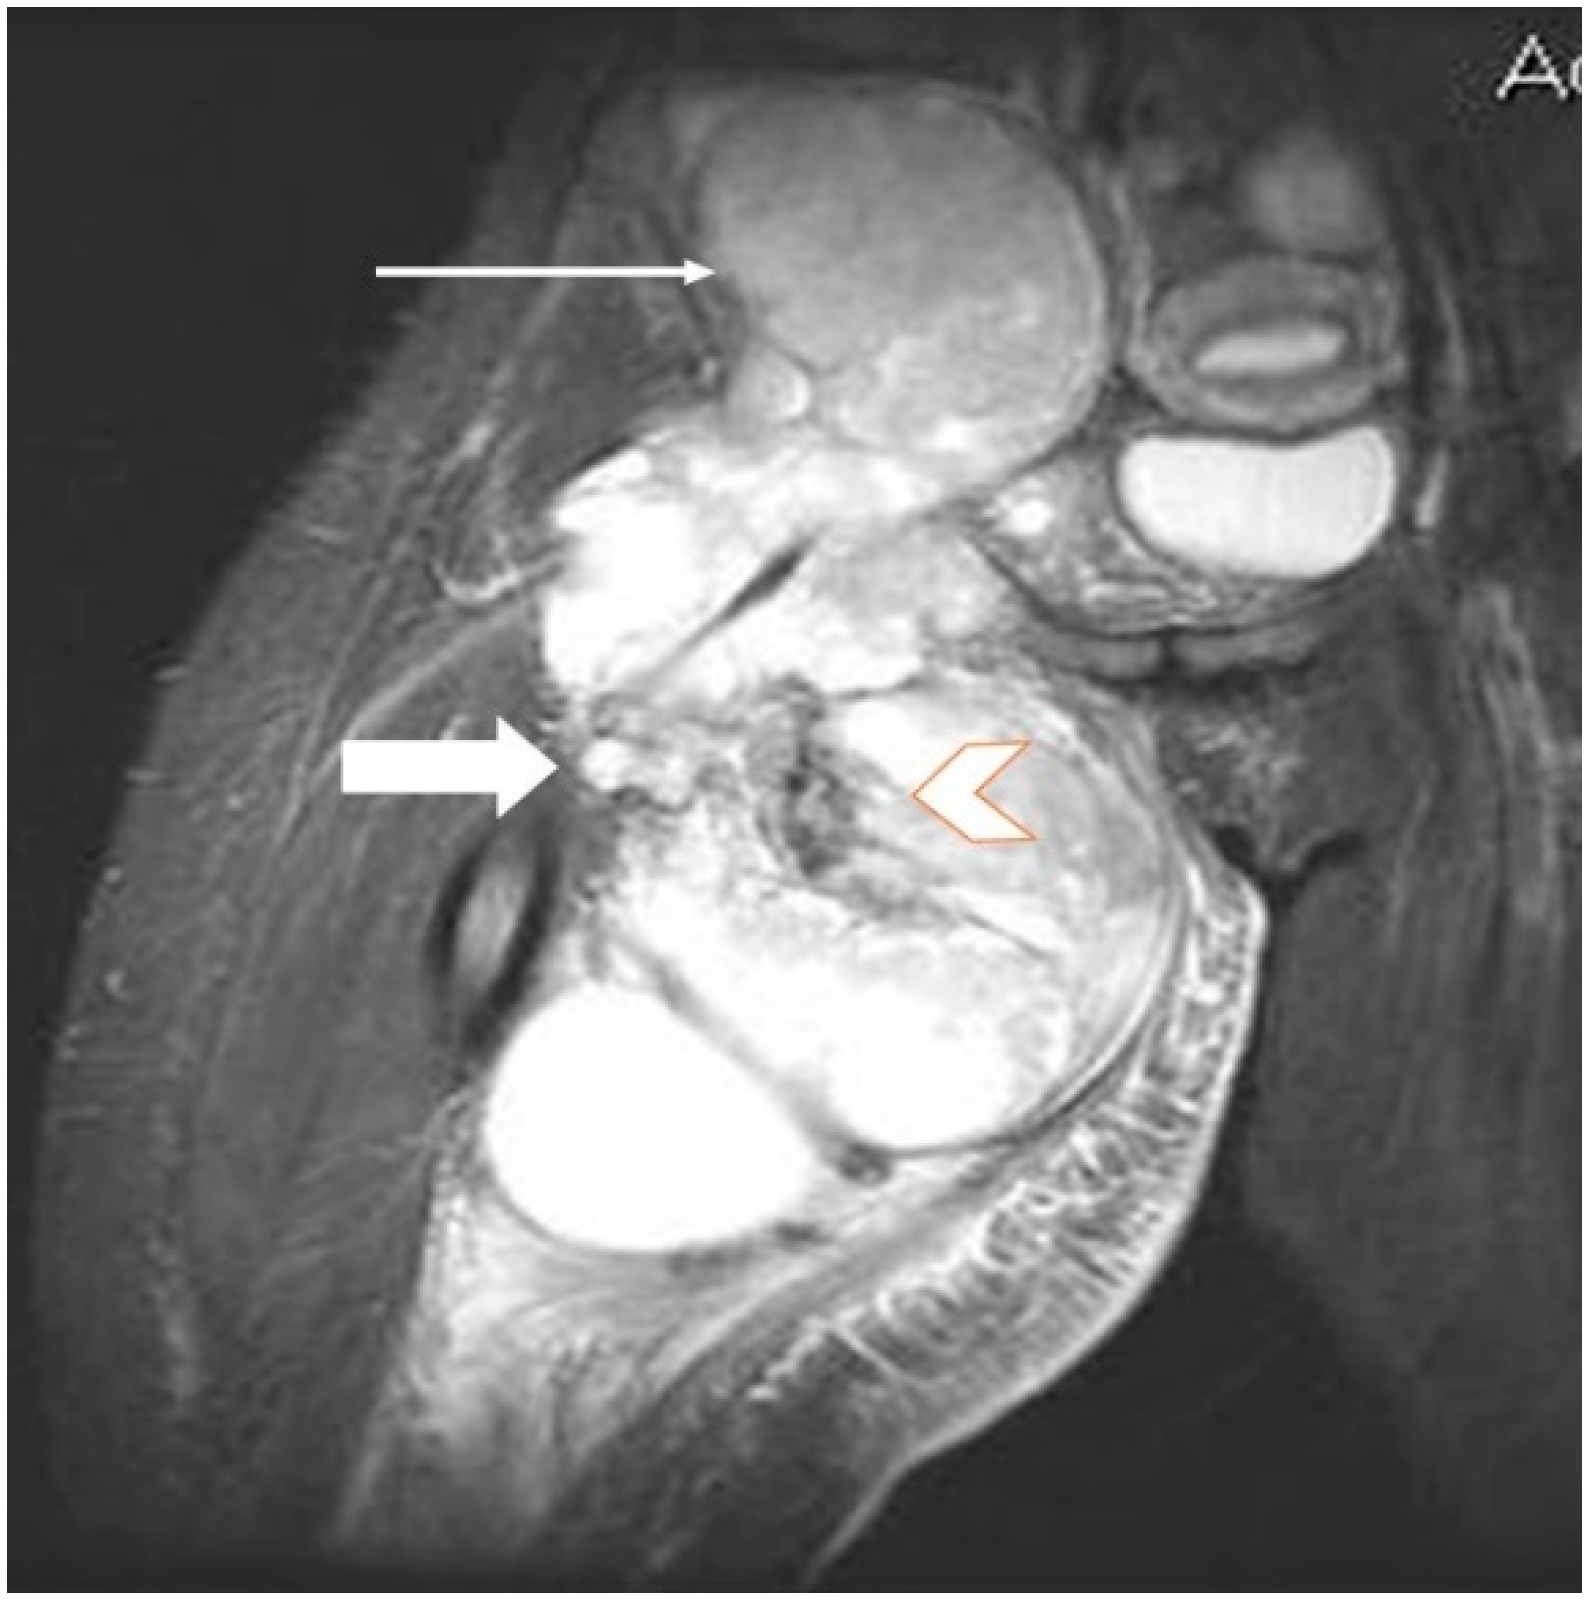

Magnetic resonance imaging (MRI) with contrast should be considered for tumors exceeding 2–3 cm and is probably the imaging method of choice for synovial sarcomas. MRI will provide valuable information regarding the extent of the tumor and the relationship with the surrounding anatomical structures; the use of a gadolinium contrast will enhance the amount of information that can be obtained since it is able to differentiate between hemorrhagic areas and solid tumoral tissue.

The T2 sequences are more specific for the diagnosis of soft tissue sarcomas and can reveal an inhomogeneous tumor, mainly with a hyperintense signal, in contrast with muscles, and the specific “triple sign” is present, representing a mixture of solid parts (medium hemorrhage and/or necrosis (high signal intensity) and calcifications or/and fibrotic areas (low signal intensity). The heterogeneity is completed by the presence of cystic parts with an aspect of fluid–fluid levels due to blood sedimentation (Figure 2 and Figure 3).

Figure 3.

Same patient as in Figure 1 and Figure 2, MR image, coronal T2 STIR (short-time inversion recovery): heterogeneous soft tissue mass showing a mixture of solid areas (line arrow), hemorrhage and/or necrosis (block arrow), calcifications or fibrosis, cystic elements and infiltration of adjacent fat. Furthermore, fluid–fluid levels (block arrow) can be observed in this figure.